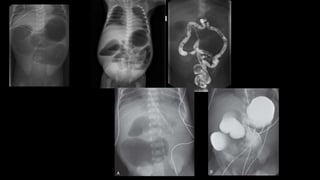

Má-rotação

Embriologia

• Radiografia de trânsito de delgado:

• 93-100% Sensibilidade má rotação

• Falso positivo:

• Flacidez ligamentar

Atresia Jejunoileal

• 46-73% das atresias

• Isquemia mesentérica intra-

uterina afetando uma ou

múltiplas áreas de intestino já

formadas.

• Fibrose cística 20%

• Gastrosquise e onfalocele 17%

Má-rotação • 1:500 • Volvo– isquemia • 75% apresentação neonatal • 10% após 1 ano de vida • Clínica • Vômitos biliosos • Distensão abdominal • Hemorragia gastrointestinal • Associação com síndromes e outras desordens congênitas • Atresia duodenal/jejunal • Estenose • Pâncreas anular • Hirschsprung • Intussuscepção

• Radiografia detrânsito de delgado: • 93-100% Sensibilidade má rotação • Falso positivo: • Flacidez ligamentar

Atresia Jejunoileal • 46-73%das atresias • Isquemia mesentérica intra- uterina afetando uma ou múltiplas áreas de intestino já formadas. • Fibrose cística 20% • Gastrosquise e onfalocele 17%